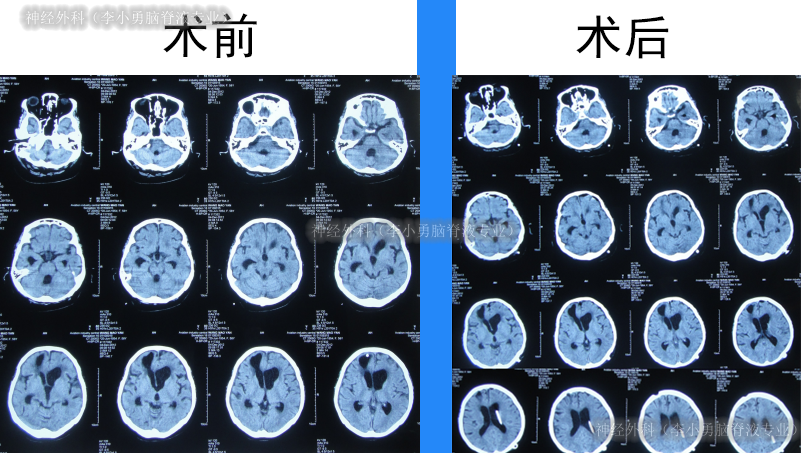

脑脊液各项化验均达标后于2012年12月4日,进行脑室腹腔分流术,术前术后头颅CT(图-19)。

图-19:术前术后头颅CT